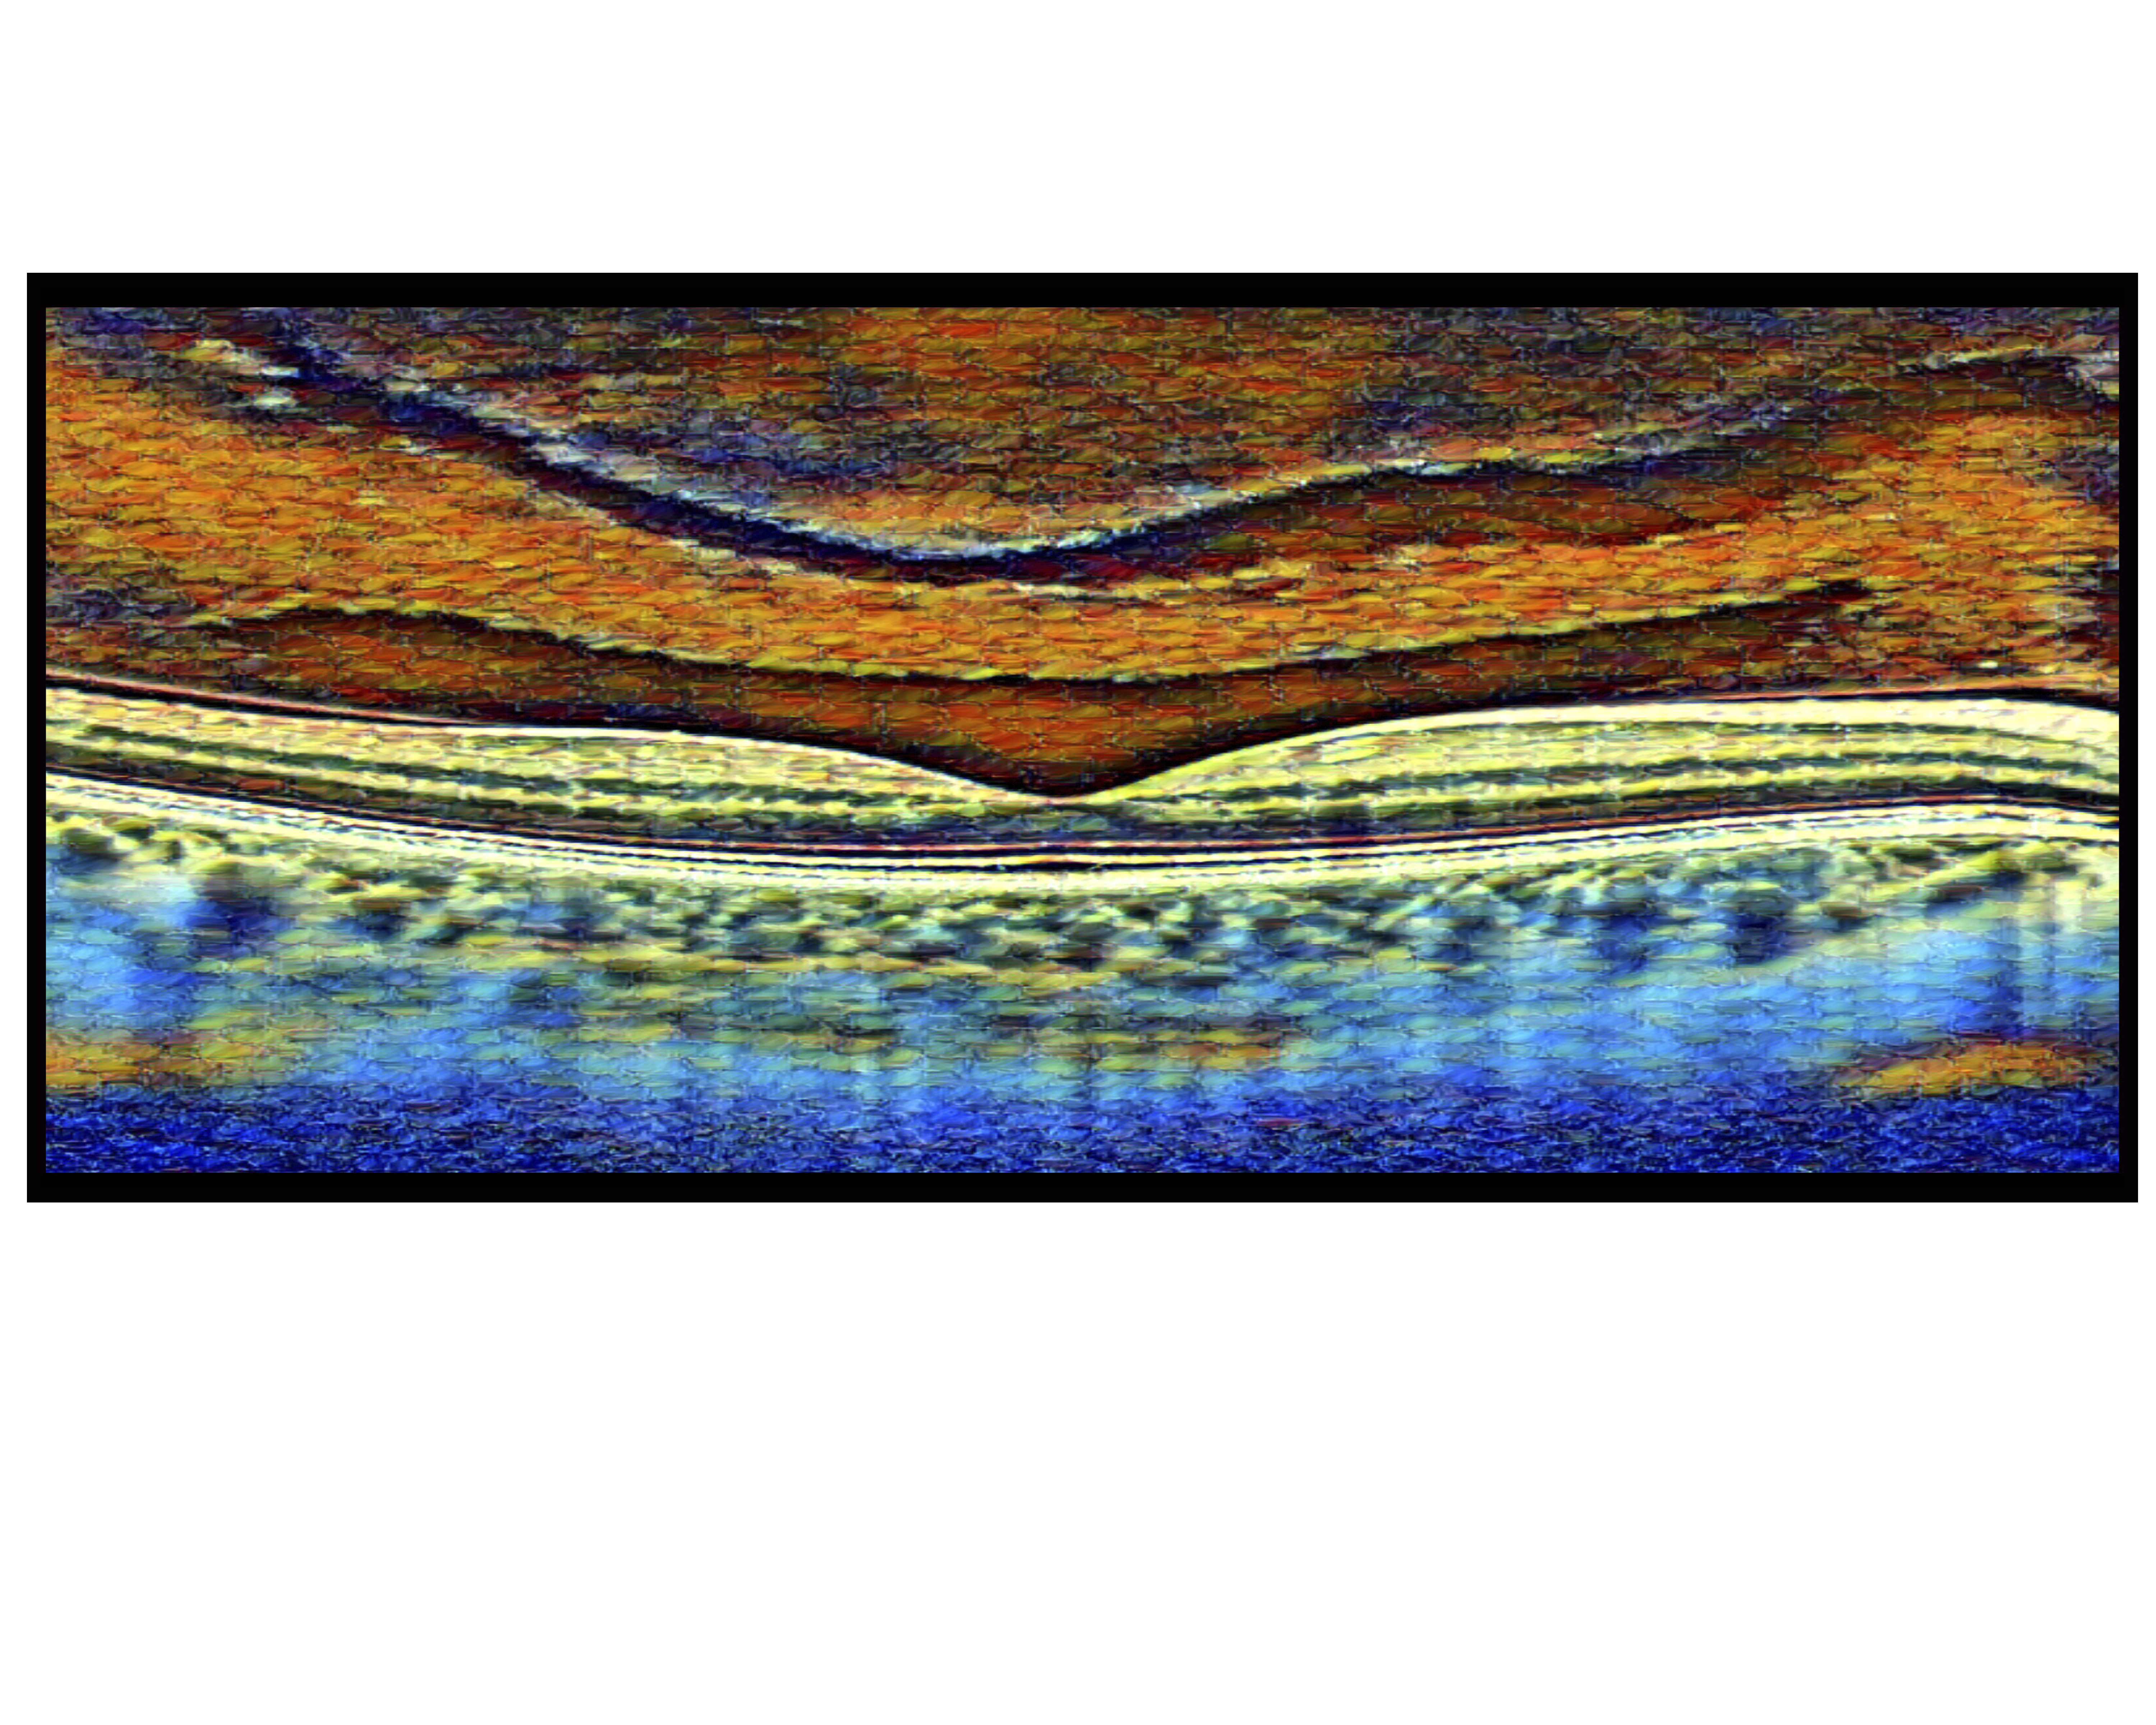

PVD at Sunset Presented by Harold Rodriguez, OCT-C This photograph received First Place in the category "The Eye As Art" and was displayed in the 2024 OPS Exhibit. Filed Under Retina OPS Photo